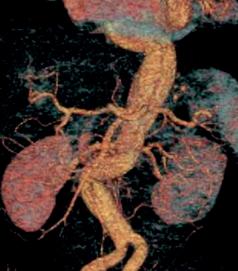

In contrast to CEA, the treatment of abdominal aortic aneurysms (AAAs) and performance of randomized trials do not occur with routine vigor. Performance of open vs. endovascular clinical trials have only occurred in public healthcare systems, both in the U.K. and the U.S. Just look at the results of the EVAR 1 (United Kingdom endovascular aneurysm repair 1) and DREAM (Dutch randomized endovascular aneurysm management) trials to assess quality of AAA repair in the VA. In the EVAR 1 trial, the 30-day operative mortality was 1.8% in the endovascular and 4.3% in the open repair groups. In the DREAM trial, the operative mortality rate was 4.6% in the open repair group and 1.2% for endovascular repair.9,10 With results similar to the other trials, operative mortality was lower with endovascular repair at 30 days compared to open repair but the mortality rate of veterans was markedly less in the endovascular group at 0.5%. A 3% reduction in open mortality was noted compared with other trials.11 The OVER (Open versus endovascular repair) trial is an example of research and clinical outcomes for veterans with AAAs to acknowledge the quality present within the VA system. The VA vascular surgery community can be proud of the outcomes achieved in a challenging population. Direct comparison to the community in clinical trials and real-world data suggest veterans receive care that meets or exceeds community standards (see footnotes at vsweb.org/TBD).